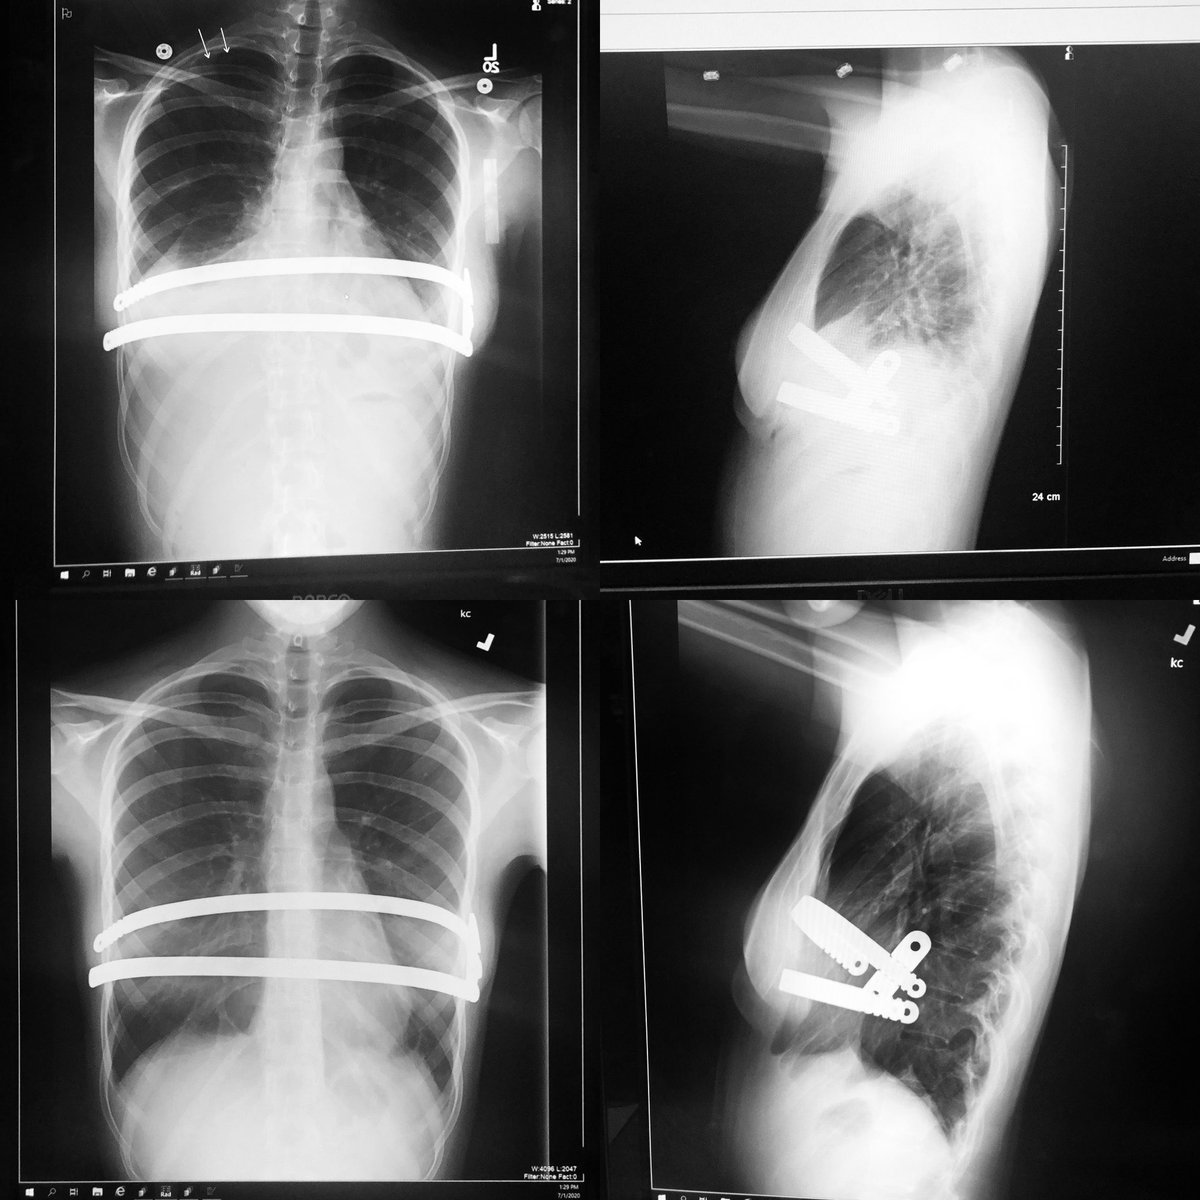

Guys! Check out the six week difference in my child’s lungs! God is so good! Top is six weeks ago, bottom is now!!

shedavi33's tweet image. Guys! Check out the six week difference in my child’s lungs! God is so good! Top is six weeks ago, bottom is now!!